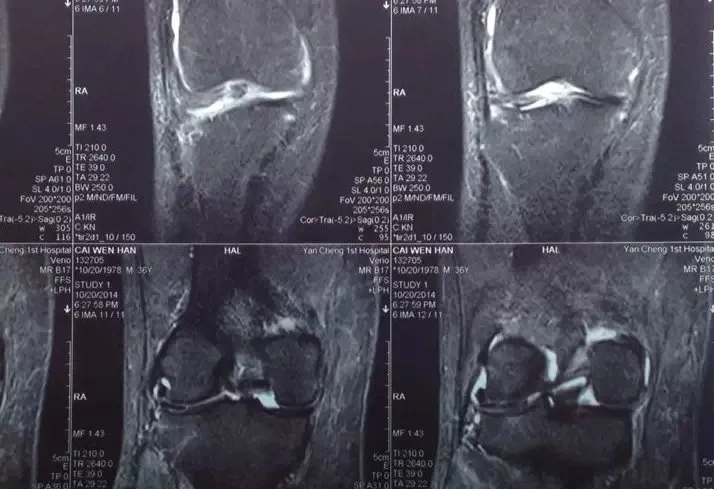

◎ MRI

對(duì)于半月板損傷首選的檢査是MRI,其診斷準(zhǔn)確率高達(dá)90%以上。根據(jù)MRI可進(jìn)行半月板撕裂的分度,除了能夠較好的顯示半月板,亦能清楚的顯示關(guān)節(jié)囊、前后交叉韌帶以及關(guān)節(jié)骨軟骨等結(jié)構(gòu)的病變。